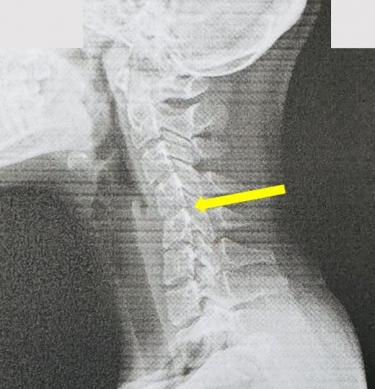

長期低頭滑手機,頸椎呈現滑脫情況(箭頭指處)。(照片員榮提供)

〔記者林碧珠員林報導〕一名20歲女大學生,長期滑手機,頸部痠痛僵硬,經員榮醫院神內科主任葉宗勳X光檢查發現頸椎弧度消失,呈現﹁僵硬直線﹂甚至滑脫,此乃俗稱的「手機頸」。 葉主任說,健康頸椎應有自然的﹁C字...